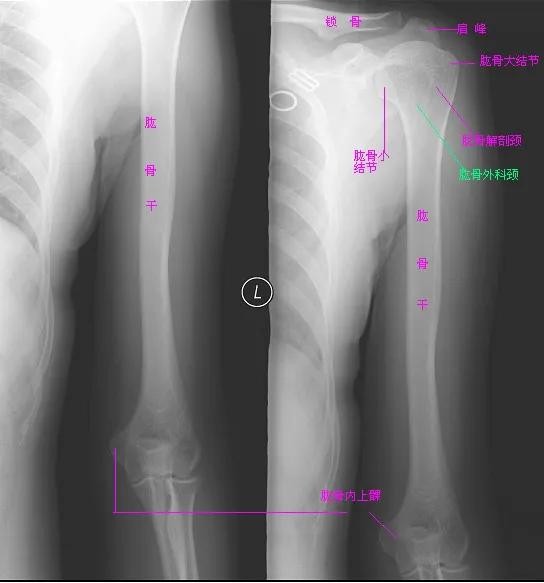

一、肱骨正常解剖

肱骨是自由上肢骨之一,是臂的长骨,分为一体两端,膨大的上端为半球形的肱骨头,与肩胛骨的关节盂相关节,头的周围稍缩窄,叫做解剖颈,颈的外侧和前方,各有一隆起,分别称为大结节和小结节。肱骨上端与体交界处骨稍细,叫外科颈,是外伤骨折的易发部位。肱骨体上端呈圆柱形,下端呈三棱柱形,中部外侧有三角肌粗隆。体的后面有桡神经沟。肱骨上端与肩胛骨形成肩关节,下端与桡骨和尺骨形成肘关节。

二、肱骨拍摄体位

1.肱骨正位:患者仰卧摄影床上,患侧上肢伸直,手掌朝上,上臂紧贴床面,肱骨长轴与床面长轴一致,其上下范围包括肩关节与肘关节。

2.肱骨侧位:患者坐于摄影床一侧,患侧上臂紧贴床面,手臂向外侧与躯干部分分开,前臂内旋肘关节弯曲,拇指向上,使肱骨内、外上髁相互重叠呈侧位。其上下范围包括肩关节与肘关节。

三、肱骨X线图像显示

在X线片上可以看到肩关节、肱骨、肘关节、锁骨、肱骨大小结节、肱骨解剖颈、肱骨外科颈。